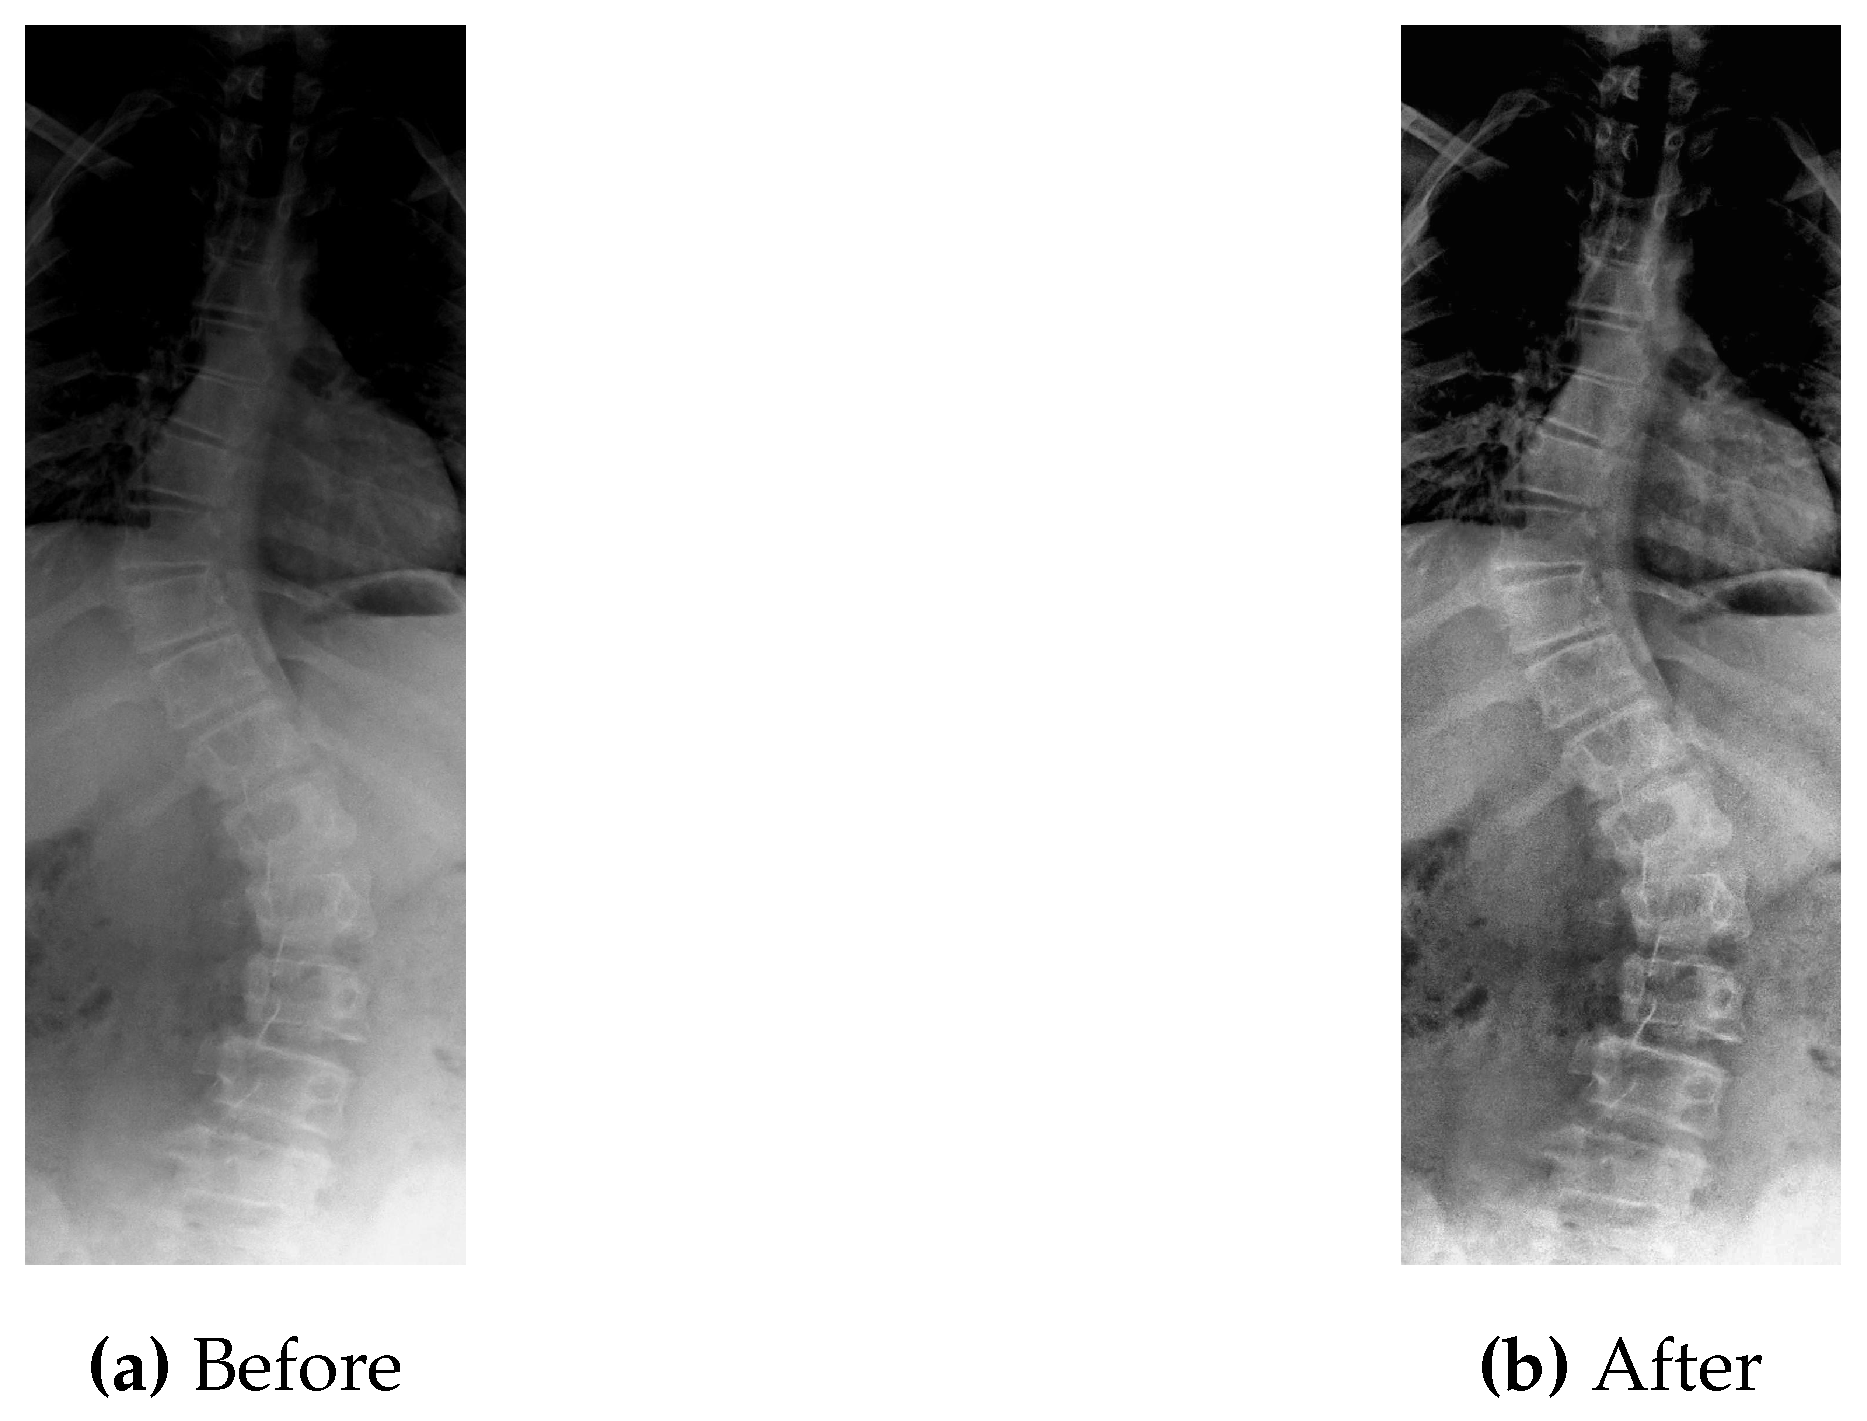

Figure 5 shows the original picture in which small details are unclear due to the low value of contrast.

As can be seen in Figure 5, the CLAHE enhanced image has significantly improved contrast as compared to the original image shown in Figure 5. These pre-processed images are then used as input for the step of data augmentation to generate more data, as described next.

Taking the bench mark dataset into consideration, first of all it is gone through the process of contrast improvement (pre-processing) with the parameter values as clip limit of 2.0 and tile grid size of 8. After that final pre-processed image is obtained. An instance of pre-processed image is shown in Figure 14.

Figure 5. Original vs Pre-processed Image.

Figure 14. Before and After Pre-processing.